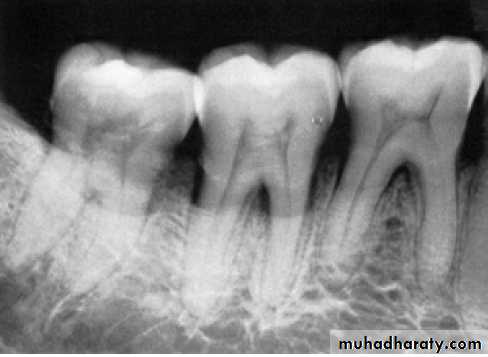

Radiographic Examination:

Radiographs are valuable for the diagnosis of periodontal disease,

estimation of severity, determination of prognosis, and evaluation

of treatment outcome.

The radiographic survey should consist of a minimum of 14

intraoral films and 4 posterior bitewing films.

Panoramic radiographs are a simple and convenient method of

obtaining a survey view of the dental arch and the surrounding

Structures.

The interdental bone normally is outlined by a thin, radiopaque line

adjacent to the periodontal ligament (PDL) and at the alveolar crest,referred to as the lamina dura.

In conventional radiographs, periapical and bitewing projections

offer the most diagnostic information and are most commonly used

in the evaluation of periodontal disease.

Pattern of bone loss:

Several investigators have analyzed the distance from the CEJ tothe alveolar crest.

The height of interdental bone may be reduced, with the crest perpendicular to the long axis of the adjacent teeth (horizontal bone loss), or

angular or arcuate defects (angular, or vertical, bone loss)

could form.